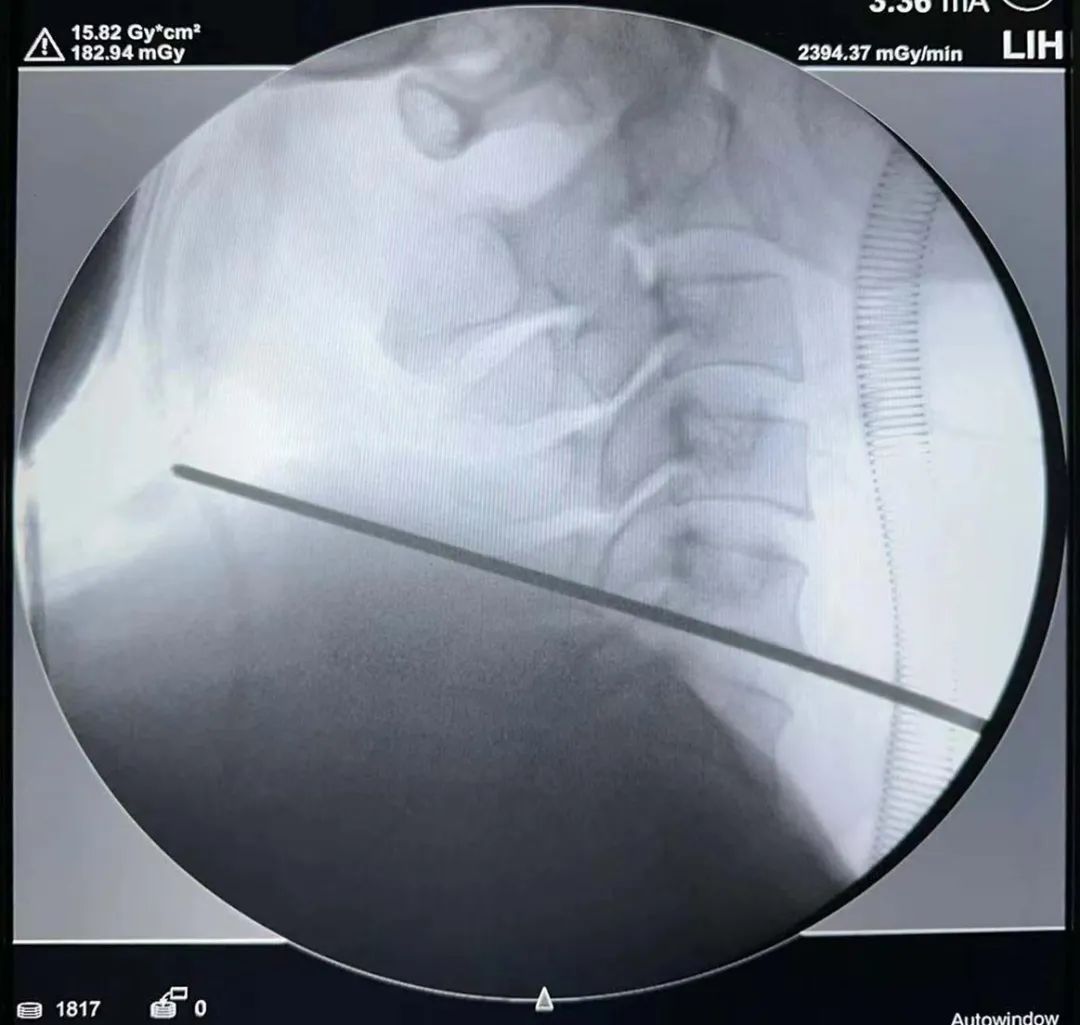

術(shù)中影像

體位透視——

節(jié)段確認(rèn)——